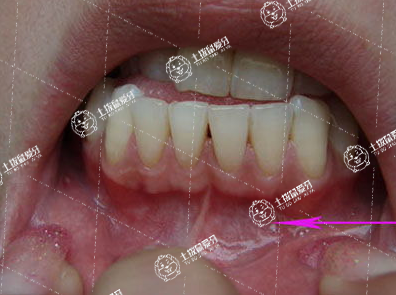

地包天即反頜,要視骨骼畸形程度進行不同的處理,如果僅牙齒畸形,則簡單進行正畸矯正即可,如果伴隨嚴重的骨骼畸形,則應該正畸正頜聯(lián)合治療。牙齒地包天矯正治療常規(guī)步驟為:首診、矯正方案制定以及矯正后復查保養(yǎng)。一般而言,牙齒地包天矯正治療分為以下步驟進行:

地包天牙齒矯正的最佳年齡和價格